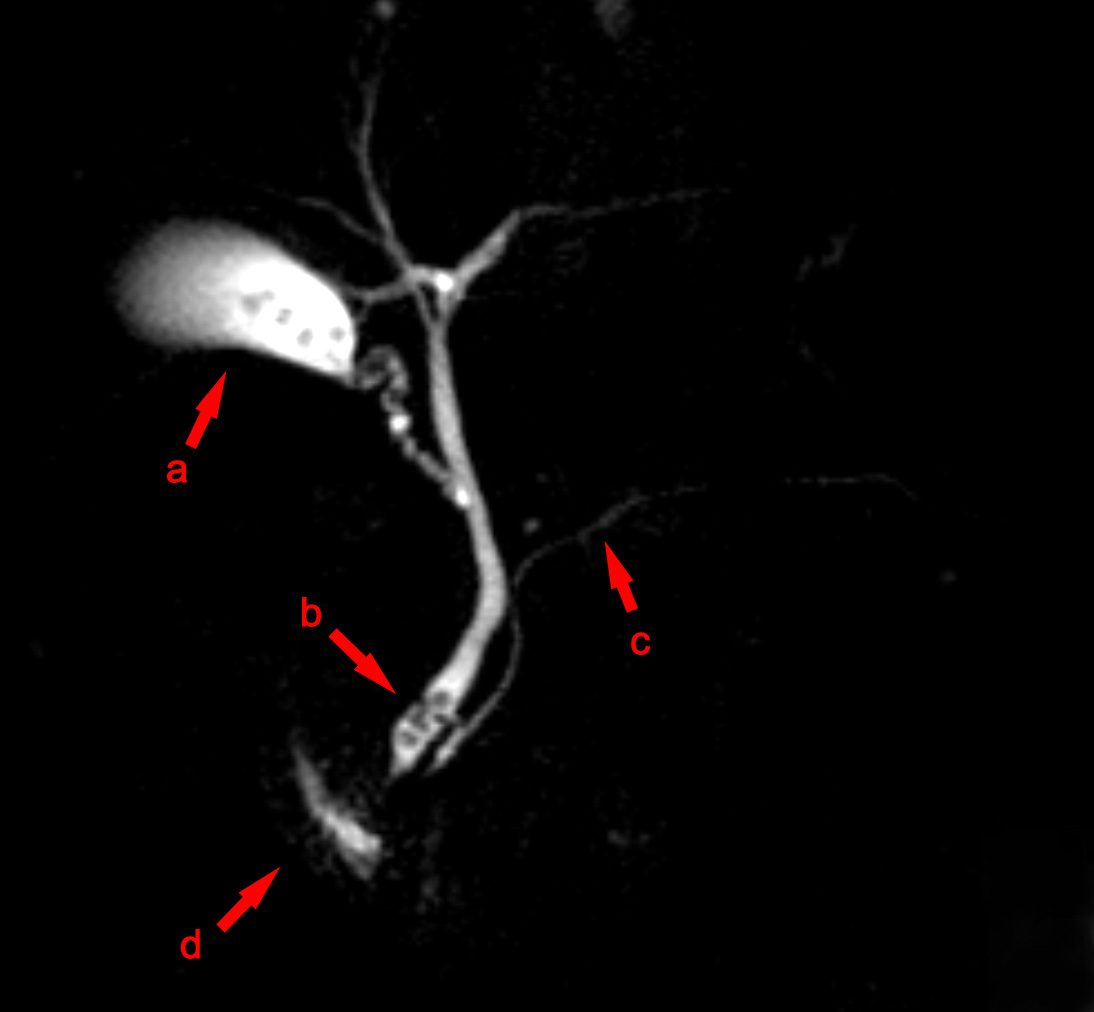

MRCP scan showing stones in the common bile duct — choledocholithiasis

Advanced — Non-Invasive

MRCP

Magnetic Resonance Cholangiopancreatography — a non-invasive MRI scan producing detailed road-maps of the bile ducts and pancreatic duct. Used when CBD stones, Mirizzi's syndrome, or complex bile duct anatomy is suspected. No radiation, no endoscope.